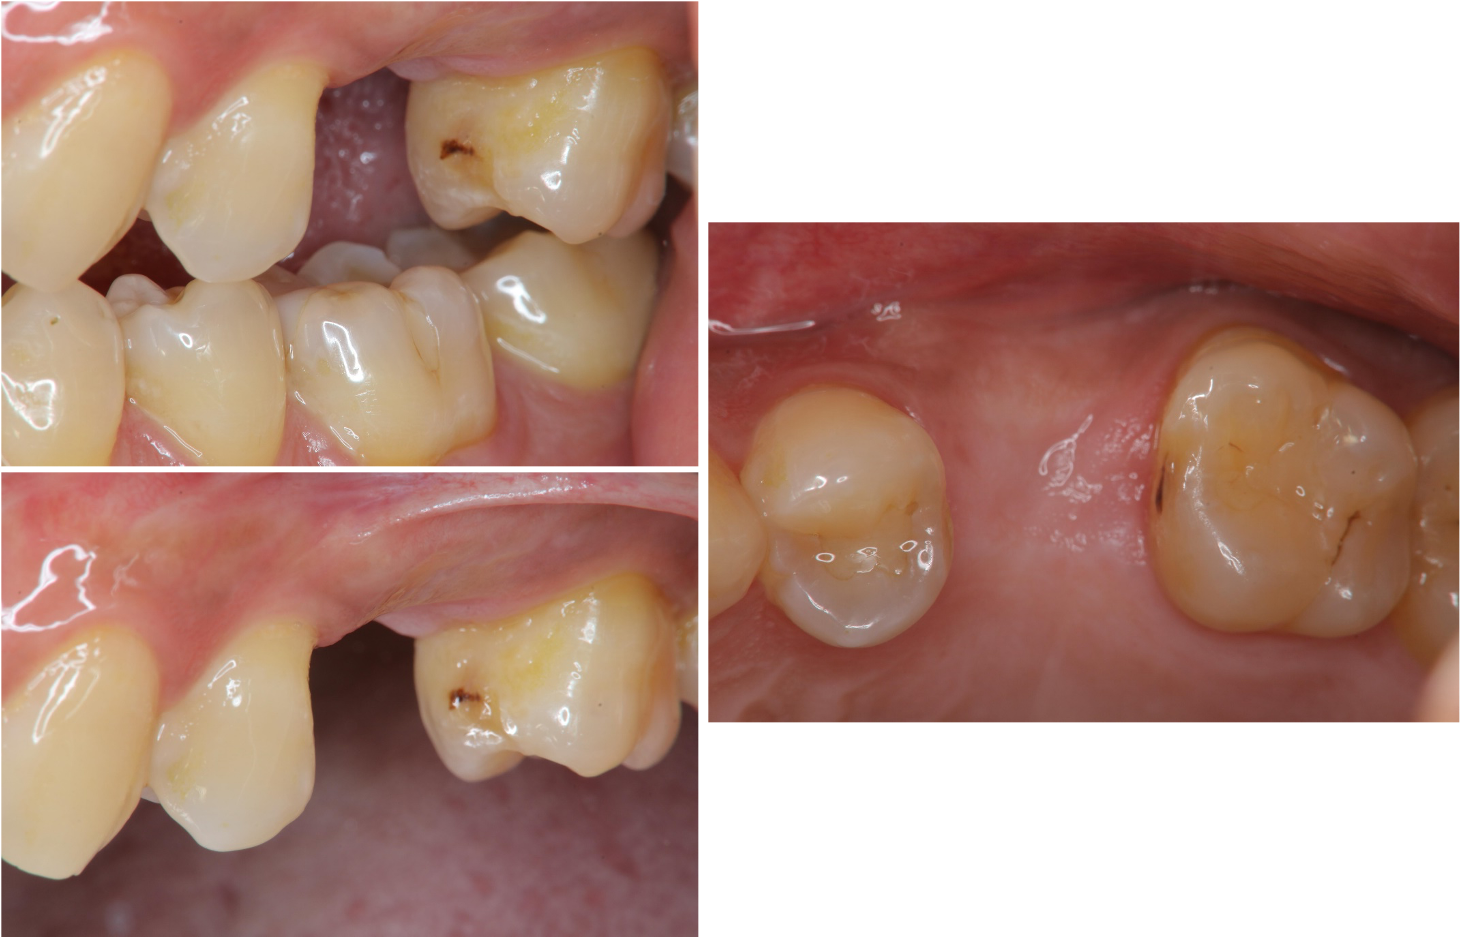

治療前,左上顎第二小臼齒缺牙